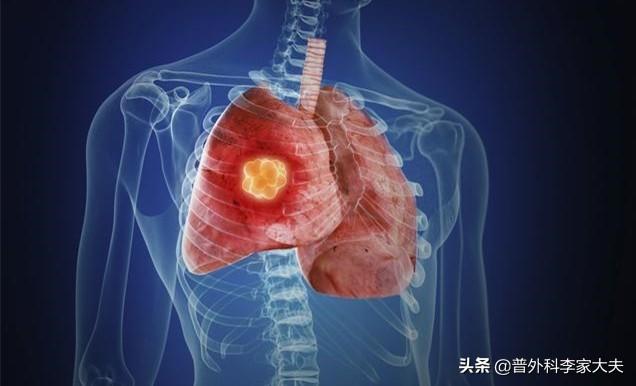

Le cancer du poumon, ou carcinome bronchogénique primaire, carcinome bronchopulmonaire primaire, est la tumeur maligne primaire la plus fréquente des poumons, provenant de la muqueuse ou des glandes bronchiques. En fonction des lésions histologiques, il peut être divisé en carcinome à petites cellules et en carcinome non à petites cellules. Les symptômes cliniques sont le plus souvent insidieux et se manifestent principalement par une toux, des expectorations, une hémoptysie et un amaigrissement. Une détection précoce, un diagnostic précoce et un traitement précoce ont un meilleur pronostic !

Pourquoi, la plupart du temps, le cancer du poumon est-il détecté à un stade avancé ? C'est parce qu'il n'y a pas de symptômes typiques du cancer du poumon dans ses premiers stades. Un symptôme typique signifie que s'il existe un certain symptôme, il est probable qu'il s'agisse d'une maladie spécifique. Cependant, les symptômes du cancer du poumon à un stade précoce ne sont pas évidents, et même si certains symptômes apparaissent, ils ne seront pas associés au cancer du poumon. Le cancer du poumon à un stade précoce est généralement détecté lors d'examens médicaux, et ces patients représentent moins de 20 % du total.

Le cancer du poumon est la tumeur maligne primaire la plus fréquente des poumons. Il s'agit principalement d'une tumeur des cellules épithéliales des bronches, des bronches fines et des alvéoles, etc. Comme de nombreuses personnes ont déjà atteint un stade moyen ou avancé lorsqu'elles découvrent le cancer, le taux de survie à 5 ans est inférieur à 20 %. Chez de nombreuses personnes, le cancer du poumon est découvert à un stade moyen ou avancé, de sorte que le taux de survie à 5 ans est inférieur à 20 %.

Le cancer du poumon est une tumeur maligne qui se développe sur la muqueuse des bronches ou des alvéoles pulmonaires. Son apparition est liée à un tabagisme important et prolongé, à l'exposition à certains agents chimiques cancérigènes et à une diminution du système immunitaire. En particulier, le risque de cancer du poumon chez les adultes qui ont beaucoup fumé pendant longtemps est beaucoup plus élevé que chez les non-fumeurs. Il est donc très important que les non-fumeurs ou les fumeurs arrêtent de fumer le plus tôt possible pour prévenir le cancer du poumon.

Les premiers symptômes du cancer du poumon sont classés en type périphérique (cancer survenant au bord du poumon) et en type central (cancer survenant dans les bronches près du hile) en raison des différentes localisations du cancer du poumon. Le cancer du poumon central se développe souvent dans la lumière bronchique, ce qui entraîne un rétrécissement de la lumière bronchique, une atélectasie ou une pneumonie obstructive, et des symptômes tels qu'une toux persistante, la présence de sang dans les expectorations, une oppression thoracique et un essoufflement.